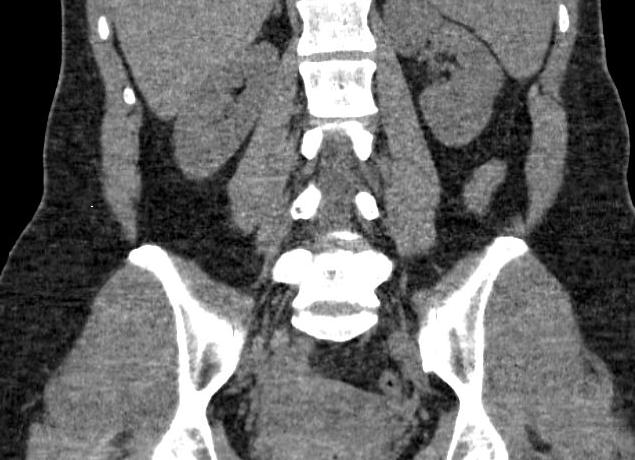

Простым и информативным способом оценки состояния ребенка в течение третьего триместра гестации, в первом (во время схваток) и втором (при потугах) периодах родов является мониторинг сердечной деятельности и сокращений матки матери. С какой недели делают КТГ? Исследование может проводиться с двадцать восьмой недели, но часто наиболее верные показатели удается получить только с тридцать второй недели. Это эффективный и безопасный метод диагностики, который не имеет противопоказаний, поэтому будущие мамы могут не волноваться ни о своем здоровье, ни о благополучии малыша.